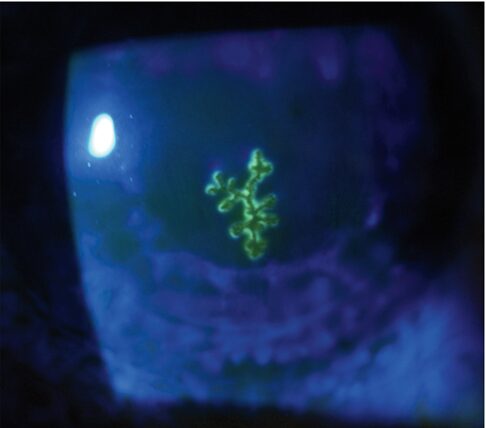

単純ヘルペス樹状角膜炎:深層前層板角膜移植術(部分厚角膜移植)術後症例です。

来院時の左眼の矯正視力は0.25だった。その後細隙灯検査により角膜充血と分枝上皮潰瘍(角膜移植片の影響)が明らかになった。コバルトブルーフィルターを通した照明下で観察された角膜のフルオレセイン染色(下画像)により樹状潰瘍が視覚化された。

以上より「単純ヘルペス樹状角膜炎」と診断された。